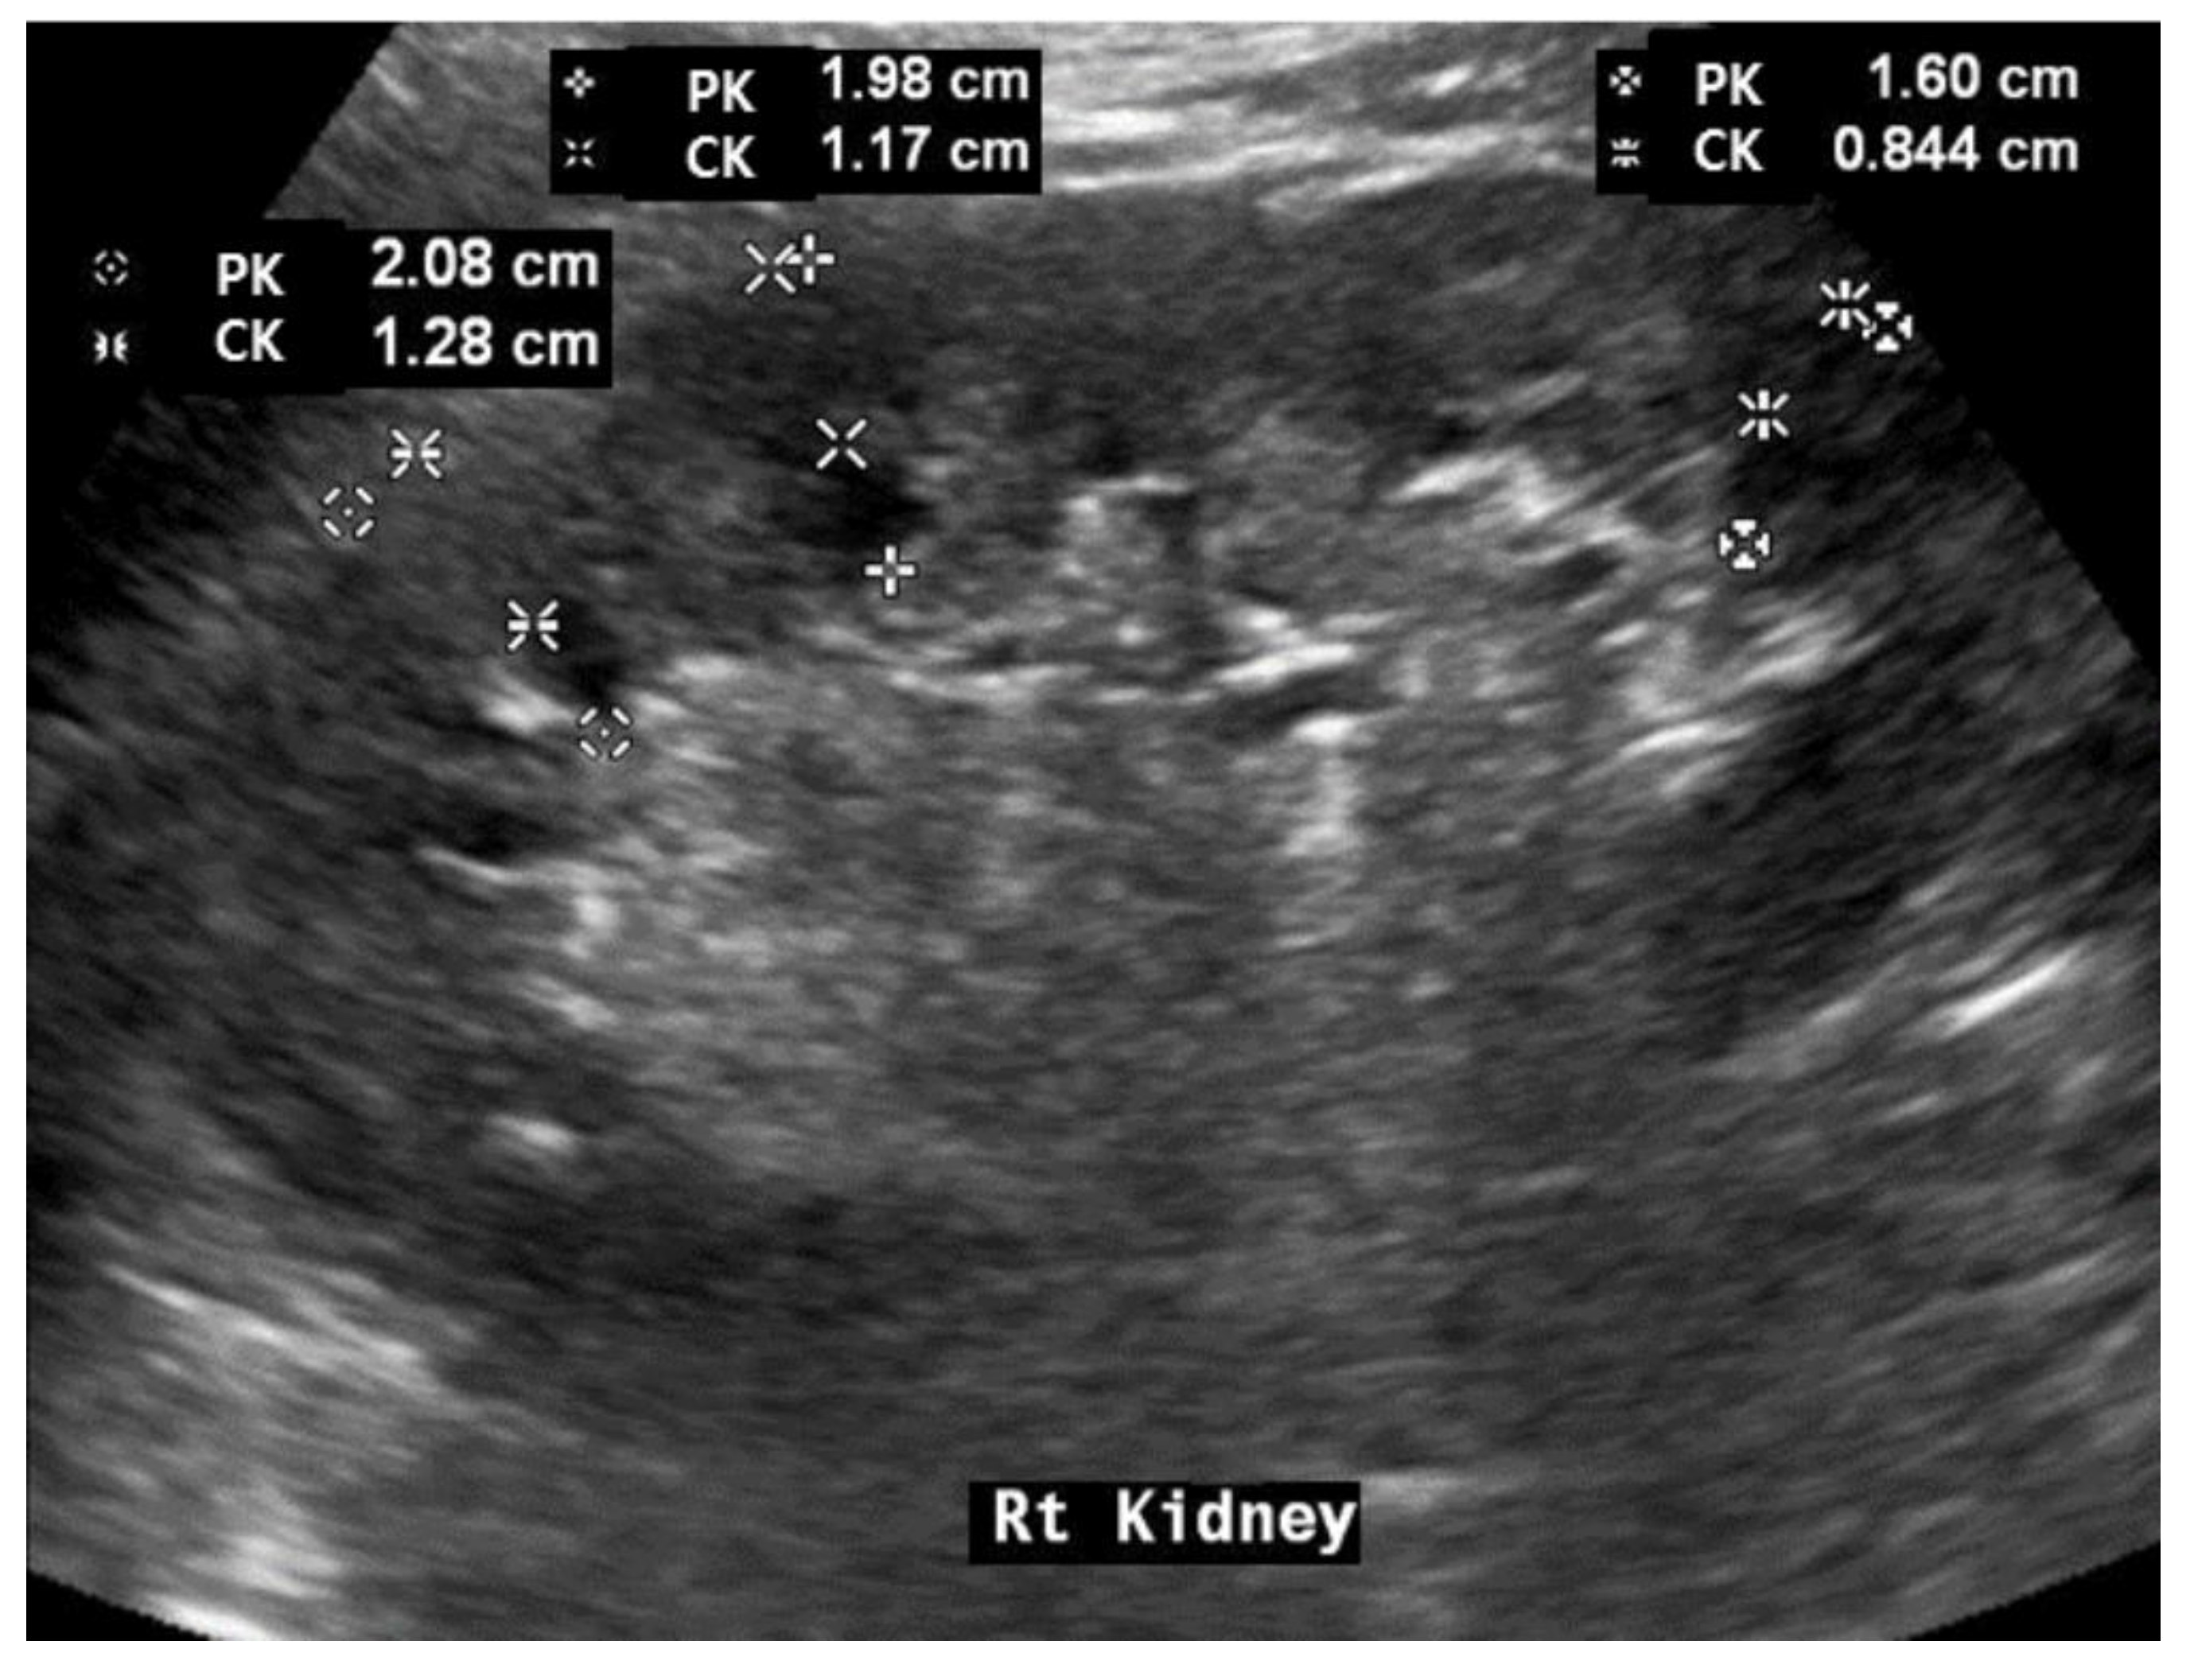

2.4. Renal Ultrasonography Examinations

| RL (cm) | 10.45 ± 0.94 (7.8–13.4) | 10.37 ± 0.95 | 10.55 ± 0.93 | 0.141 |

| CK (cm) | 0.66 ± 0.17 (0.31–1.41) | 0.65 ± 0.16 | 0.69 ± 0.19 | 0.049 |

| PK (cm) | 1.42 ± 0.24 (0.84–2.45) | 1.38 ± 0.23 | 1.49 ± 0.27 | 0.001 |

| CK/PK | 0.46 ± 0.65 (0.29–0.70) | 0.47 ± 0.06 | 0.46 ± 0.07 | 0.447 |

| CK/RK | 0.06 ± 0.01 (0.04–0.12) | 0.06 ± 0.01 | 0.06 ± 0.02 | 0.074 |

| PK/RK | 0.14 ± 0.02 (0.08–0.21) | 0.13 ± 0.02 | 0.14 ± 0.02 | 0.005 |

| RH | 6.44 ± 0.53 (5.28–8.99) | 6.41 ± 0.54 | 6.48 ± 0.51 | 0.150 |

| CKH | 1.03 ± 0.26 (0.52–2.11) | 1.38 ± 0.23 | 1.06 ± 0.28 | 0.147 |

| PKH | 2.22 ± 0.37 (1.45–3.47) | 2.16 ± 0.36 | 2.29 ± 0.37 | 0.007 |